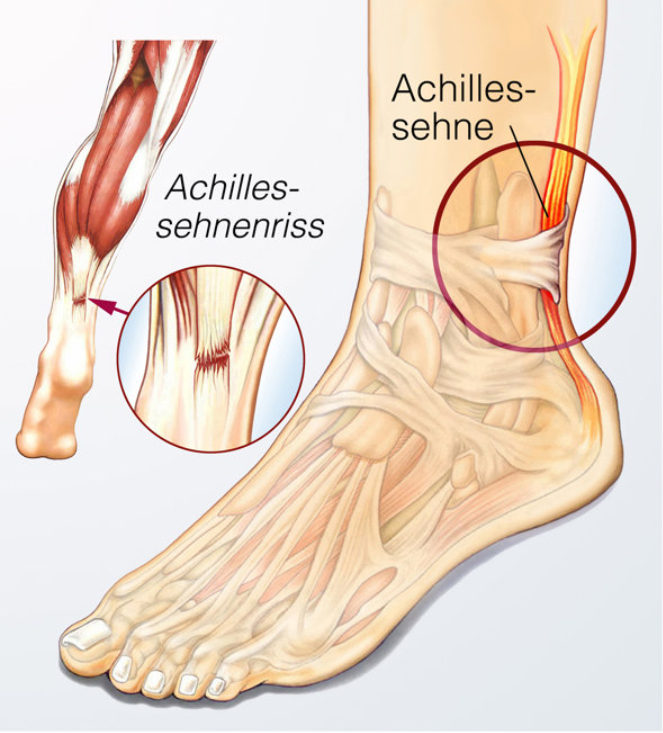

勇士队医疗团队通过核磁共振影像确认,穆迪的伤情属于髌腱部分撕裂,而非更严重的完全断裂。这一诊断结果对球员的康复前景具有关键意义。医学专家Brian Sutterer在播客中解析了伤情机制,指出当肌腱在离心收缩状态下突然承受向心收缩的极限负荷时,极易发生断裂。这种受伤模式与跟腱断裂的机制相似,但幸运的是穆迪的伤情尚未达到完全断裂的程度。